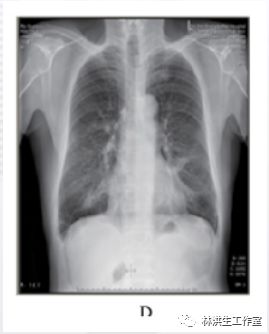

D: 2016 年 6 月 23 日复查双侧肺肿物较发病时明显缩小。